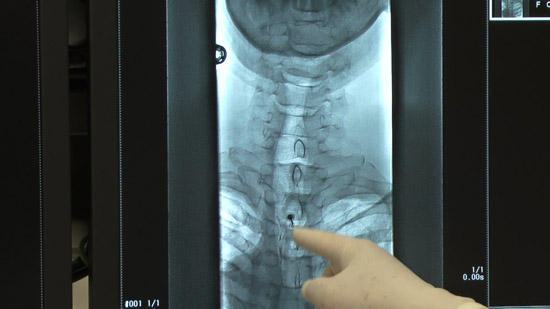

(2)Set the positioning by checking the puncture site along with the image on the radiological screen.

(4)Conduct an epidural puncture by the resistance loss method, checking with the image on the radioscopy screen.

※Inject the contrast medium and check it again. Capture a confirmation image at the same time.

Check with the image on the radioscopy screen.

Check subjective physical condition of patients after 10 cc infusion and capture a projectional image.

Capture projectional images at the end of infusion.